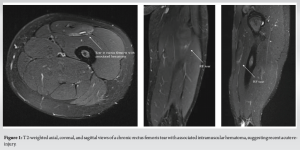

A healthy 21-year-old female collegiate softball player was participating in sprint conditioning in August of 2022 when she experienced quadriceps tightness and a tearing sensation in her left hip. She continued to play that fall season despite ongoing left thigh pain. Her injury was managed conservatively, guided by her athletic trainer and physical therapy (PT). She continued to have pain that worsened with running, lunging, and squatting, and was unable to play in the Spring 2023 season. After a summer of rest, she returned to school for fall conditioning but continued to have significant pain and sporadic ecchymosis over the left quadricep. She was unable to participate in sports. She presented to a sports medicine physician in September of 2023 and was diagnosed with hip pain secondary to a suspected labral tear. Her thigh soreness was attributed to iliotibial band syndrome and her quadriceps dysfunction to compensatory movements. She was again referred to PT. The patient progressed appropriately; an MRI arthrogram of the left hip was unremarkable. Weeks later, despite initial progress, the patient felt a tightening sensation in her left quadriceps. The pain and tearing sensation were akin to those she previously experienced, and she noticed a small mass in the proximal third of her thigh. She returned to her sports medicine physician. She had no ecchymosis or weakness with hip flexion but did have a palpable, small mass over her proximal quadriceps. This was confirmed on ultrasound; however, the extent and chronicity of the injury were not well characterized. She was diagnosed with a possibly chronic left quadriceps strain and instructed to continue PT. She sought a second opinion at our clinic. Physical examination showed a palpable mass over the left proximal thigh, significant pain with resisted hip flexion and knee extension, lateral thigh paresthesias, and a positive Tinel sign adjacent to the small mass. Her LFCN paresthesias were exacerbated by squatting. A non-contrast MRI of the left thigh (Fig. 1) revealed a partial thickness tear of the indirect head of the RF at the level of the proximal femoral diaphysis and an intramuscular hematoma, suggesting acute-on-chronic injury. The proximal origins of the RF tendon were intact. No other injury was noted.